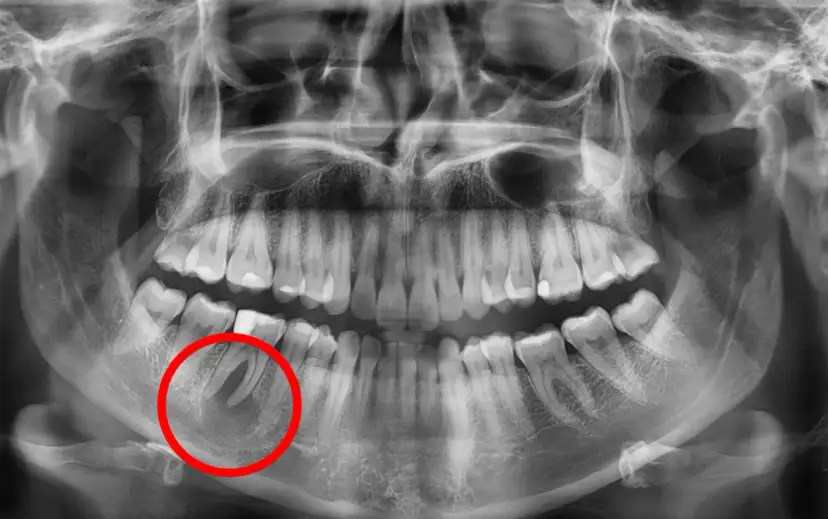

Torbiel pod zębem - dowiedz się, czym jest, jakie daje objawy i powikłania. Sprawdź, kiedy boli, jak diagnozować i leczyć, by uniknąć zagrożeń. Czytaj!